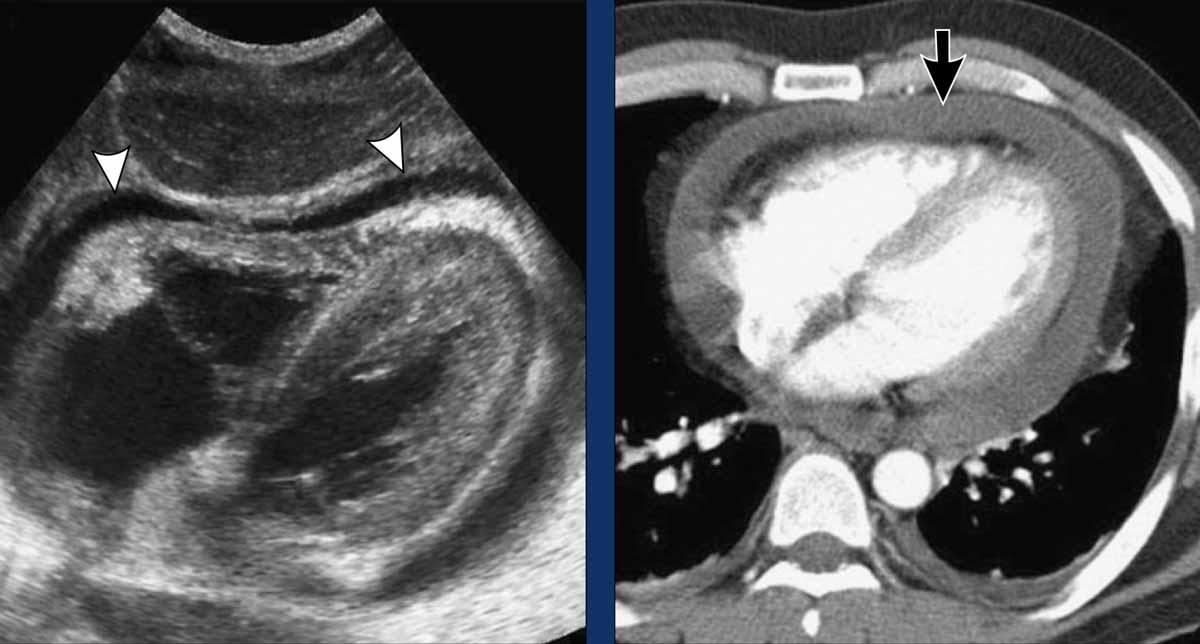

Bệnh nhân nam 52 tuổi nhập viện với chẩn đoán viêm màng ngoài tim cấp do nhiễm trùng và đau thượng vị cấp.

Hình ảnh học

- Siêu âm cạnh ức trái cho thấy tràn dịch màng ngoài tim kèm dày màng ngoài tim (đầu mũi tên). Không phát hiện bất thường ở ổ bụng.

- CT có thuốc cản quang xác nhận sự hiện diện của tràn dịch màng ngoài tim được bao quanh bởi màng ngoài tim dày và ngấm thuốc (mũi tên).

Dẫn lưu màng ngoài tim thu được dịch tiết viêm, nhiều khả năng có nguồn gốc virus. Sau khi điều trị viêm màng ngoài tim, các triệu chứng ở bụng của bệnh nhân dần dần thuyên giảm.

Bệnh cảnh lâm sàng

Bệnh nhân nam 49 tuổi bị chèn ép tim, biểu hiện chủ yếu bằng đau bụng trên.

- Siêu âm túi mật theo mặt cắt dọc cho thấy thành túi mật dày lan tỏa (đầu mũi tên). Mặc dù hình ảnh này có thể gợi ý viêm túi mật, nhưng sự vắng mặt của sỏi túi mật và tình trạng căng giãn túi mật gợi ý nguyên nhân ngoại sinh.

- Siêu âm gan theo mặt cắt ngang cho thấy tĩnh mạch chủ dưới (IVC) giãn và các tĩnh mạch gan giãn to (đầu mũi tên), phù hợp với suy tim phải.

- Siêu âm cạnh ức trái xác định tràn dịch màng ngoài tim lượng nhiều (mũi tên), phù hợp với viêm màng ngoài tim cấp vô căn là nguyên nhân nền.

- Hình ảnh CT của một bệnh nhân khác bị chèn ép tim, biểu hiện bằng đau bụng cấp và nôn.

CT không tiêm thuốc cản quang cho thấy tràn dịch màng ngoài tim lượng nhiều với giá trị tỷ trọng cao hơn nước (+35 HU), gợi ý tràn máu màng ngoài tim. Chẩn đoán này được xác nhận bằng chọc hút màng ngoài tim.

Nguyên nhân nền là do mới đặt máy tạo nhịp tim gần đây.

Sau khi dẫn lưu màng ngoài tim, các triệu chứng ở bụng của bệnh nhân đã thuyên giảm.